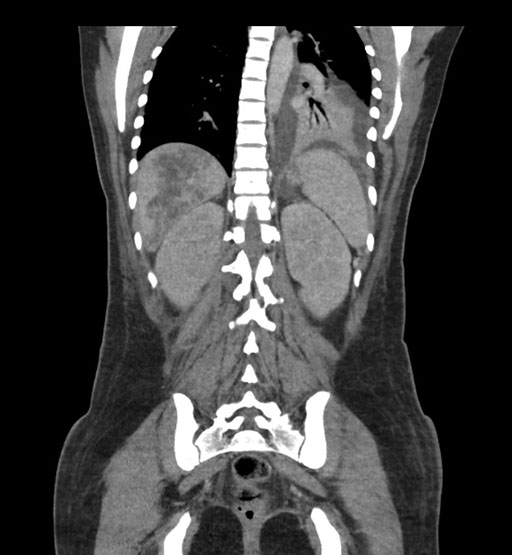

Coronal Arterial

Imaging analysis

Based on initial findings, which issue(s) would you be most concerned about?